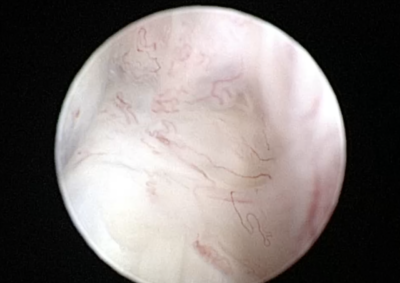

整形外科 注意 ボタンをクリックした先に、治療中および手術中の画像が説明で使用されている場合がございます。 そのような画像に弱い方は閲覧なさらないようお願いいたします。 整形外科 上腕骨外顆骨折の癒合不全 整形外科 大腿骨遠位開放および粉砕骨折 整形外科 膝蓋骨内方脱臼+前十字靭帯断裂 PGR#21+CBLO #251 整形外科 犬の前十字靭帯断裂に対するCBLO #250 整形外科 脛骨粉砕骨折 整形外科 内側鉤状突起分離症(Fragmented Medial Coronoid Process:F... 整形外科 股関節全置換術(トータル・ヒップ・リプレイスメント)#27 整形外科 橈骨固定術 #268 整形外科 橈骨固定術 #267 整形外科 橈骨固定術 #266 整形外科 股関節脱臼に対するBUSTOR #67 整形外科 脛骨粗面剥離骨折 <1234567> 症例カテゴリー 放射線治療整形外科軟部組織外科脳神経外科内科腫瘍外科救急・集中治療リハビリテーション科腫瘍内科内視鏡科脳神経科呼吸器外科中医・漢方猫の腎移植循環器科